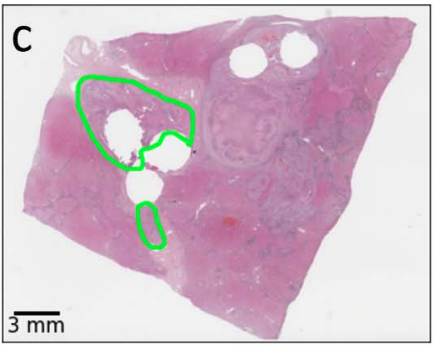

Tools in Digital Pathology

necrotic tumor

viable tumor

non-tumor

Manual coarse annotation

Computational refinement

Ground truth